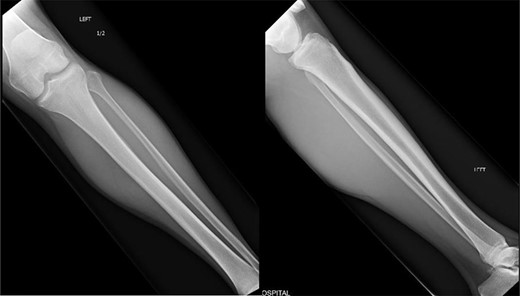

The left lower extremity demonstrated 2+ dorsalis pedis and posterior tibial pulses, and intact gross motor movement from L5 to S1. He had complete loss of sensation to the plantar aspect of his foot, with intact sensation elsewhere. His lateral and anterior compartments were soft and compressible, however his posterior compartments were tense. He had mild discomfort to palpation and passive stretch of the posterior compartments. Radiographic imaging shown in Fig. 1 ruled out trauma.

Orthogonal radiographic views of the patients left tibia and fibula. No evidence of trauma to be suspected which correlated with the patient’s history.